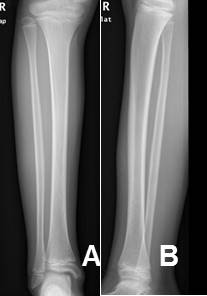

Fig 17. Hemartrosis.

A: Rx AP. Fracturas no desplazadas, ni deprimidas en los platillos tibiales.

B: Rx lateral con rayo horizontal. Nivel grasa/líquido en la región suprapatelar, por hemartrosis.

La detección de niveles liquido/líquido o líquido/grasa, son signos de compromiso intra-articular. (1, 3). (Fig 26).